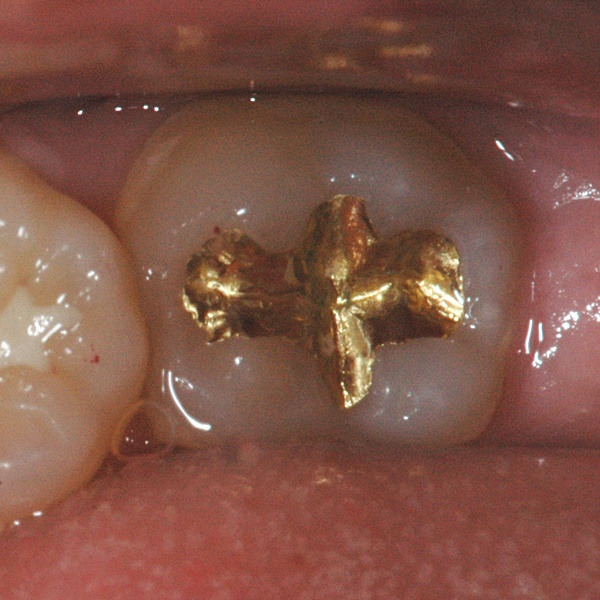

인레이/온레이는 보철물 재료에 따라 골드 인레이/온레이, 세라믹 인레이/온레이 등으로 치료가 가능합니다.

골드는 전통적으로 많이 쓰이는 재료로, 생체친화성이 좋고 강도가 우수한 것이 강점입니다. 하지만 심미적으로 치아색과 차이가 많이 나는 것이 단점이라고 할 수 있습니다. 골드 함량에 따라 가격차이가 발생합니다.